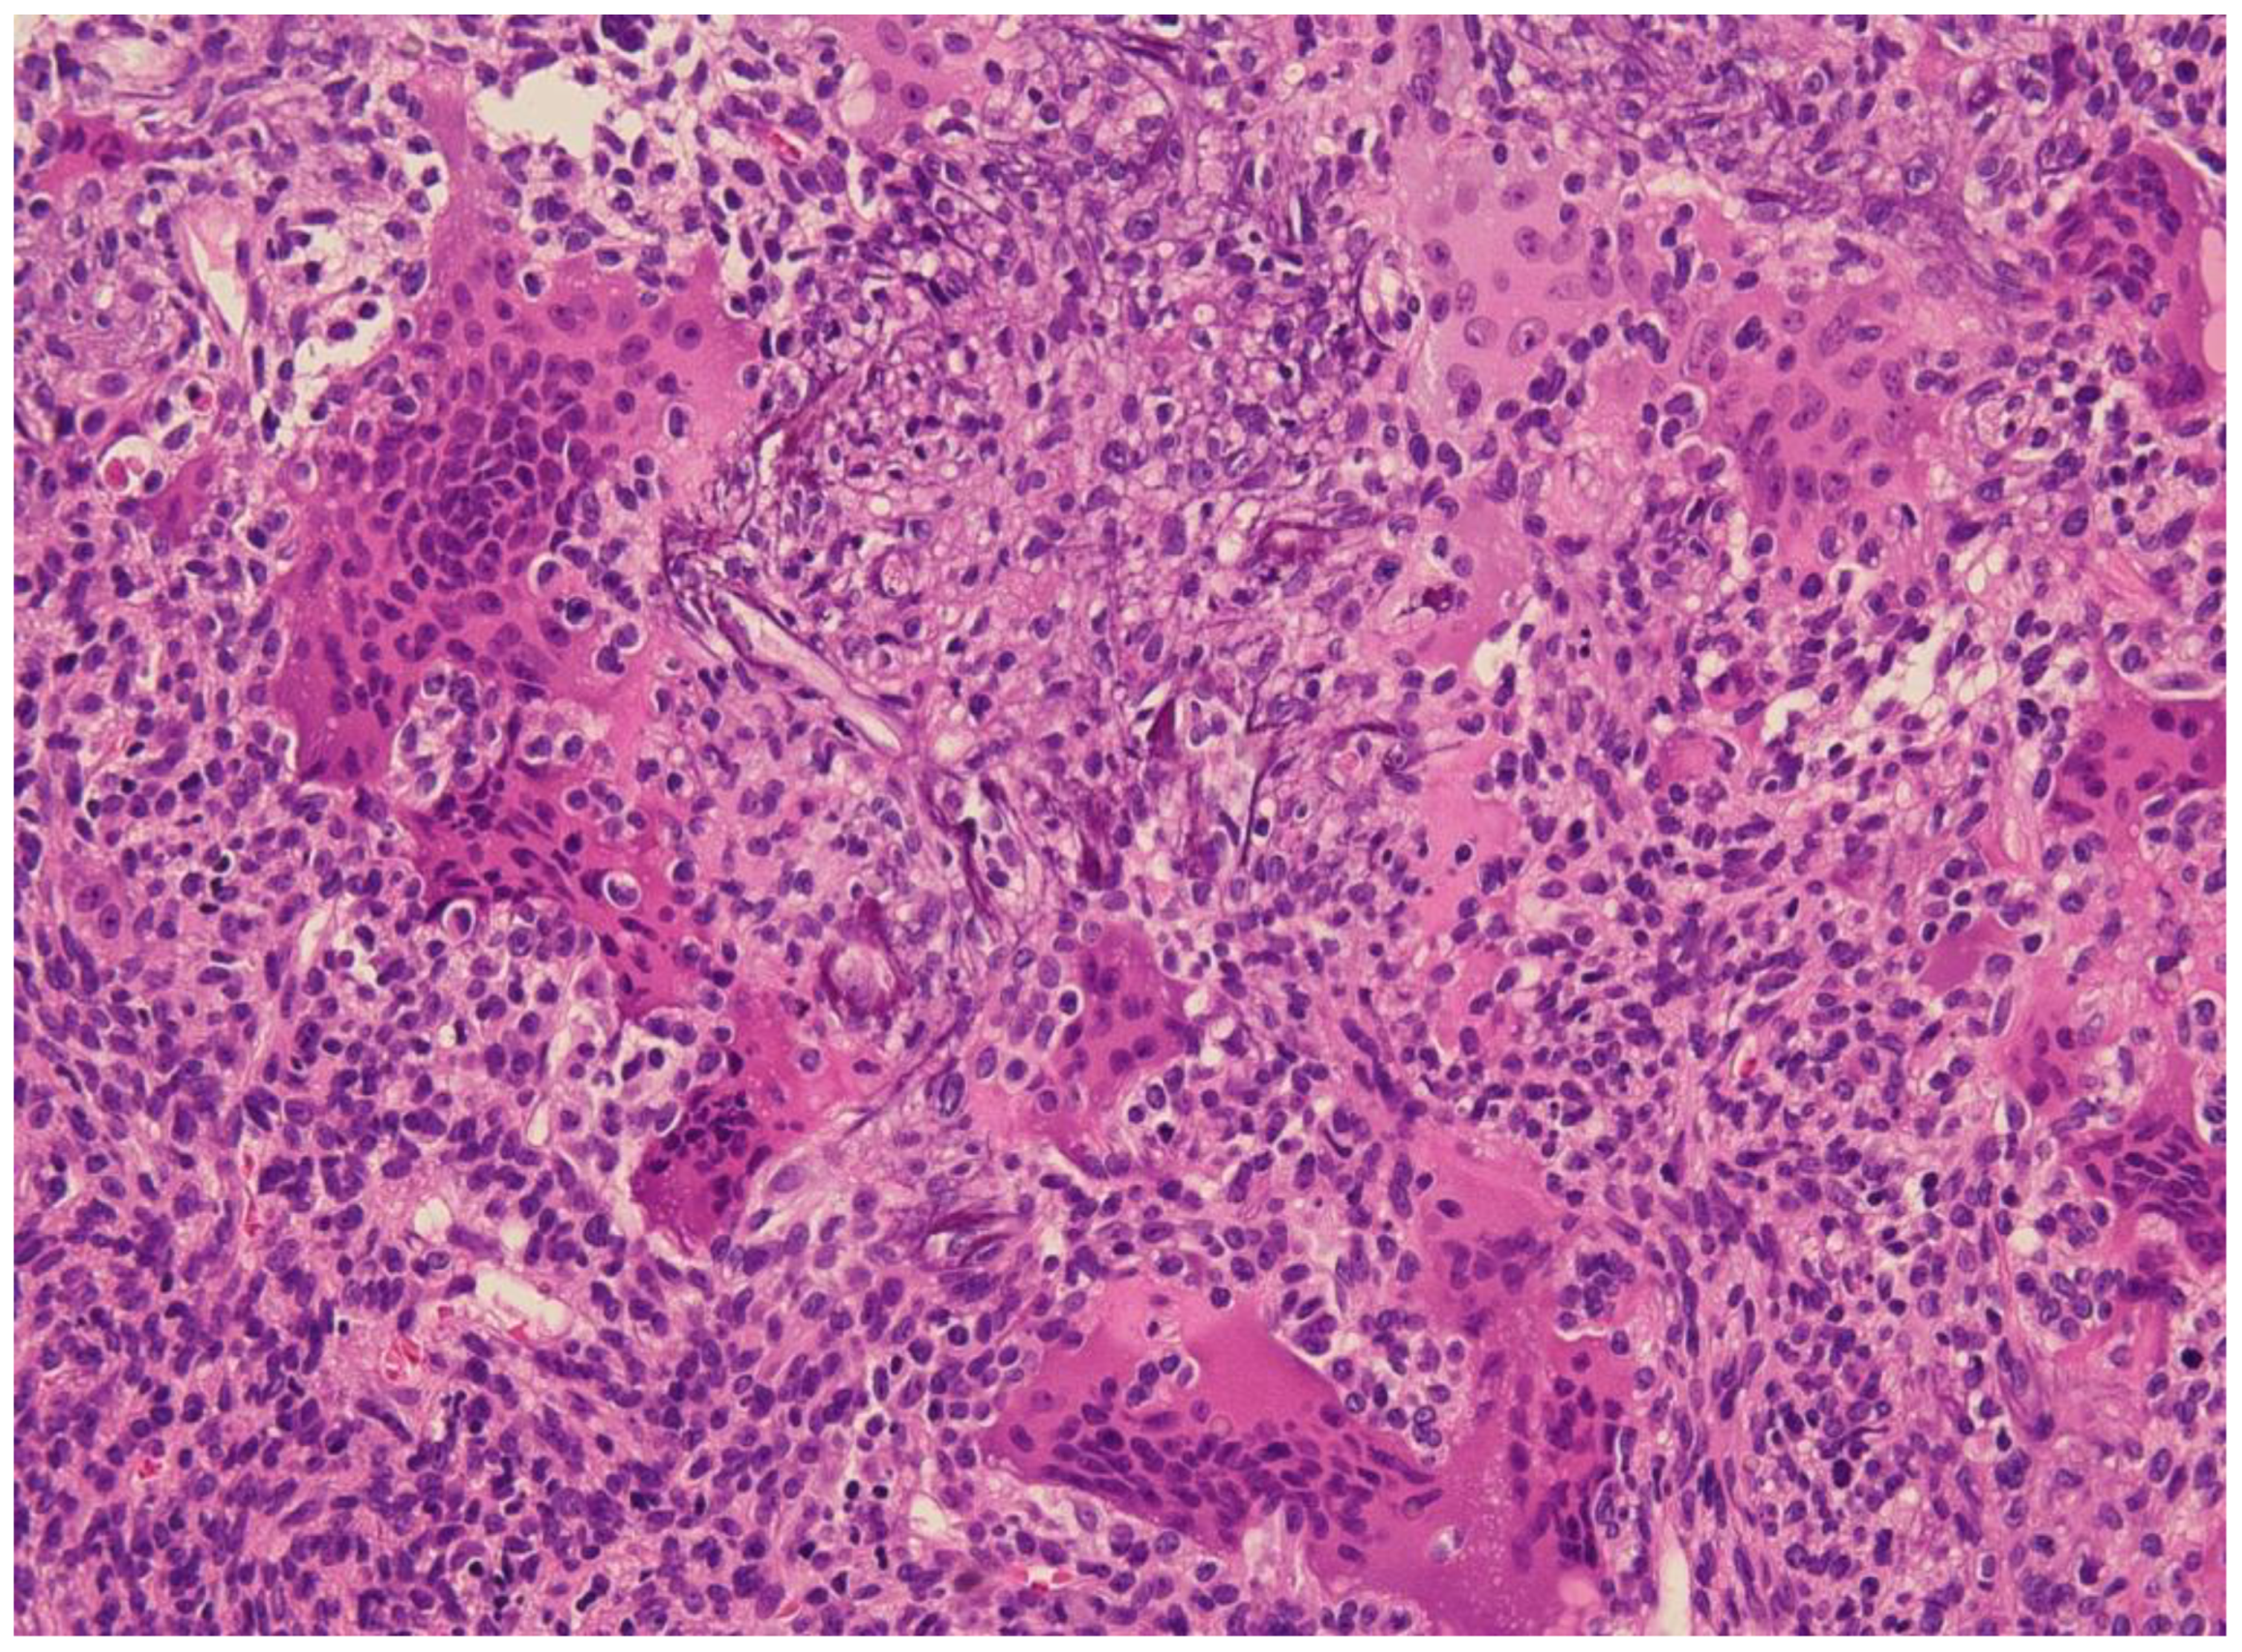

5. Histology

- Folpe, A.L.; Fanburg-Smith, J.C.; Billings, S.D.; Bisceglia, M.; Bertoni, F.; Cho, J.Y.B.; Econs, M.J.; Inwards, C.Y.; de Beur, S.M.J.; Mentzel, T.; et al. Most Osteomalacia-associated Mesenchymal Tumors Are a Single Histopathologic Entity: An analysis of 32 cases and a comprehensive review of the literature. Am. J. Surg. Pathol. 2004, 28, 1–30. [Google Scholar] [CrossRef]

- Weidner, N.; Santa Cruz, D. Phosphaturic mesenchymal tumors. A polymorphous group causing osteomalacia or rickets. Cancer 1987, 59, 1442–1454. [Google Scholar] [CrossRef]

- Agaimy, A.; Michal, M.; Chiosea, S.; Petersson, F.; Hadravsky, L.; Kristiansen, G.; Horch, R.E.; Schmolders, J.; Hartmann, A.; Haller, F. Phosphaturic Mesenchymal Tumors: Clinicopathologic, Immunohistochemical and Molecular Analysis of 22 Cases Expanding their Morphologic and Immunophenotypic Spectrum. Am. J. Surg. Pathol. 2017, 41, 1371–1380. [Google Scholar] [CrossRef]